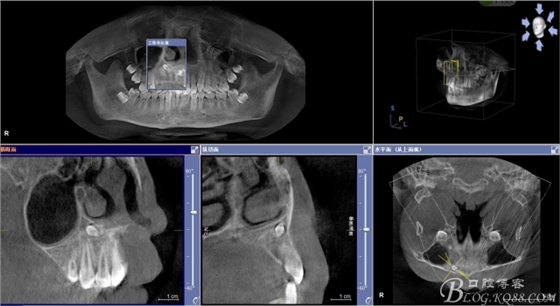

患者、男、15歲,主訴:牙齒不整齊,要求正畸治療。專科檢查:見圖1 ,cbct檢查:11與21之間,12與13之間各有異倒置多生牙,尤其以21根尖區(qū)多生牙位置高,與患者家屬充分溝通,患者同意拔除兩顆多生牙。簽知情同意書。

圖3.cbct影像檢查:12與13根尖上方也有一顆倒置多生牙,接近鼻底。

圖4.三維重建影像:12根尖區(qū)的多生牙位置更高。手術(shù)難度大